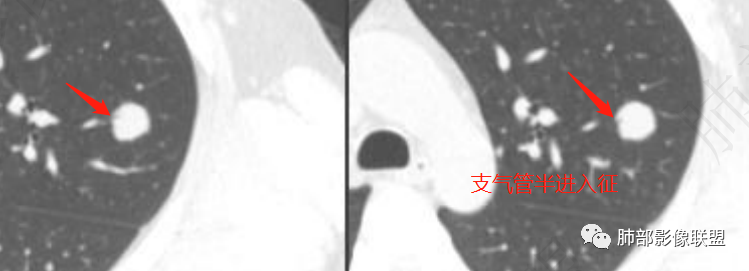

中年男性,左肺上叶孤立性结节,增强见持续性强化,内见少量坏死区,分界尚清,部分支气管进入再堵,可以考虑得疾病有,1、PSP,女性多见;单发类圆形实性结节影,边缘光滑,病灶大小不一,PSP密度常较均匀,少数可有砂砾状钙化。“空气新月征”、“晕征”及“血管贴面征”等特性表现,增强明显强化;2、错构瘤:肺内最常见良性肿瘤,结节内可见脂肪成分和爆米花样钙化,比较有特征性征象,增强轻度或无强化。3、结核球:有特定好发部位,轻中度强化,周围可见卫星灶。4、曲菌球:免疫低下患者多见,可见空气新月征及晕征,增强强化不明显呈轻中度强化。5、炎性肌纤维母细胞瘤,一般边缘不光滑,可见长毛刺及深分叶,强化一般较明显。6、球形肺不张,CT外带球形肿块,无分叶毛刺,一侧紧贴胸膜,肺门侧边缘模糊,可见支气管及血管影,增强较明显强化。7、平滑肌瘤转移:女性多见,年龄40岁以上;CT边界光滑的肿块或结节,可轻度分叶,无毛刺邻近血管及支气管轻度受压,增强显著强化。8、动静脉畸形:显著强化与肺动脉相似,可见粗大的肺动脉及引流静脉。9、A肺癌(鳞癌):多发生于中老年男性患者,与吸烟密切相关,临床症状多有痰中带血:而结节多有毛刺、分叶征,囊变坏死多见,增强扫描不均匀 强化, 峰值持续时间短,对周围血管是侵及牵拉,呈血管集束征改变,多可合并纵膈淋巴结转移 。B 腺癌:多位于肺周边,界限清楚;短毛刺征、深分叶征、脐凹征、棘突征、空泡征、胸膜凹陷征、血管集束征、月牙铲等。10、类癌,周围型少见。11、涎腺类肿瘤。12、淋巴上皮瘤样癌:肿瘤多数位于胸膜下,呈类圆形及分叶状,肿块多数边缘轮廓光滑,边缘清楚,胸膜牵拉及毛刺征少见,支气管截断或狭窄,平扫肿块可见斑片状坏死低密度区,增强扫描呈不均匀中度明显强化,可见“包绕血管征”,纵隔、肺门淋巴结转移常见。13、支气管囊肿,多为囊性密度,CT值一般10-20HU,可合并感染、出血等,CT增强可轻度至明显强化。14、肺脓肿,急性病程。晨读定性良性,错构瘤可能,鉴别慢性炎性病灶(结核、真菌)

左肺病灶边缘模糊,内有血管进入和血管穿行,还有半支气管进入,内部强化中等,可见多发坏死,考虑隐球菌感染可能性更大些,鉴别错沟瘤和神经内分泌肿瘤,详见标图!

1、考虑恶性病变的征象:肚脐凹征、轻度分叶征、V征或支气管半进入征、远端局部阻塞性改变,以及递增性强化等征象,临床上半年结节有增大,腺癌可以考虑;